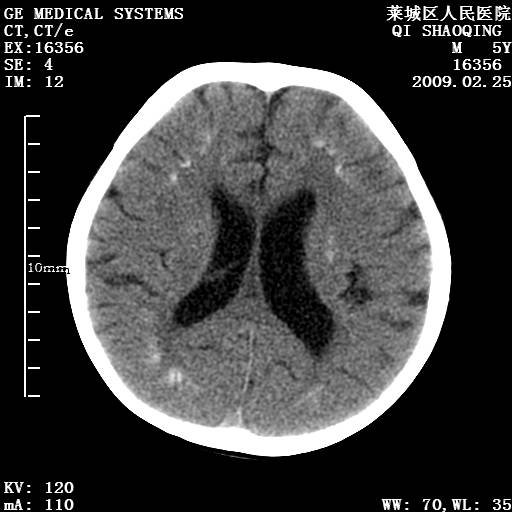

以下是引用wangzhengyuan在2009-2-28 10:22:00的发言:[br]甲状旁腺功能减退引起的脑改变.

以下是引用zsl6918在2009-2-28 10:17:00的发言:[br]首先考虑甲状旁腺功能低下所致,可结合实验室检查明确.另外需除外先天性宫内感染所致.

以下是引用余辉在2009-3-1 9:35:00的发言:[br]患者明显的肢体及智力改变,不支持fahr病,多考虑甲旁低,有可能伴有甲低(呆小症).进一步检查。